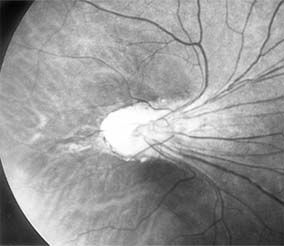

The treatment of retinopathy of prematurity is based on the classification and stage of the disease. It is important to note that a significant number of patients with retinopathy of prematurity undergo spontaneous regression. Peripheral retinal changes of regressed retinopathy of prematurity include avascular retina, peripheral folds, and retinal breaks; associated changes in the posterior pole may include straightening of the temporal vessels, temporal stretching of the macula, and retinal tissue that appears to be dragged over the disk (Figure 10-18). Other ocular findings of regressed retinopathy of prematurity include myopia (which may be asymmetric), strabismus, cataract, and angle-closure glaucoma.

Figure 10-18

Figure 10-18: Retinopathy of prematurity with stretching of the macula and straightening of retinal vessels.